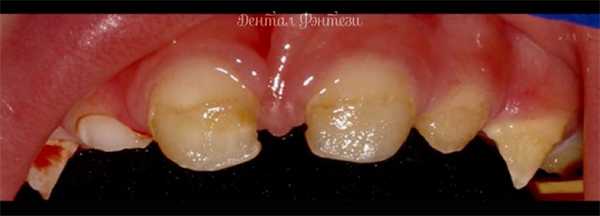

Иногда родители видят у своего ребенка странные пятна и полосочки на зубах. А иногда на зубе совсем нет эмали, она отсутствует. Молочный или постоянный зуб становится таким не со временем, а прорезывается уже с дефектом эмали. На приеме у стоматолога оказывается, что это гипоплазия зубной эмали.

Проявляется гипоплазия эмали зубов в виде различных по цвету и форме пятен. Эти пятна могут уменьшаться со временем и изменяться по цвету - светлеть. Это происходит, потому что после прорезывания эмаль продолжает минерализоваться составляющими слюны. Поэтому крайне важно избегать кислой среды слюны (ограничивайте сладкое!) и поддерживать отличную гигиену полости рта.

Также гипоплазия зубов может иметь деструктивный характер - когда можно заметить "углубление" в эмали. Такая форма гипоплазии очень часто сопровождается кариесом.

Гипоплазия эмали может быть системной - поражаются все зачатки временного прикуса. Белые или желтые пятна на передней поверхности зубов.

- апластическая форма. Один из самых тяжелых форм гипоплазии эмали зубов. Эмаль нет совсем или есть только на некоторых участках.